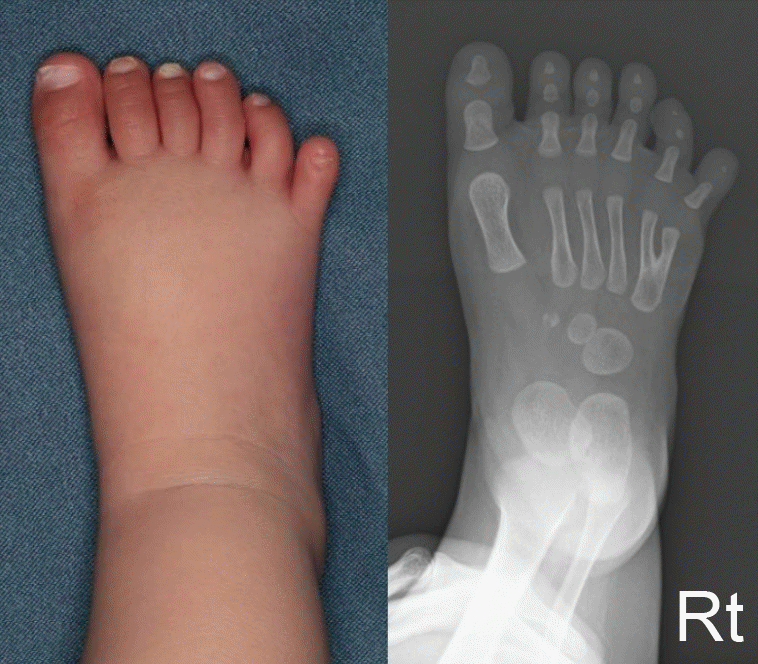

Fig. 4.

Clinical photograph and radiograph of the right foot at 9 months of age. The right foot showed postaxial polydactyly, demonstrating an asymmetric pattern of polydactyly.

The left foot had both preaxial polysyndactyly and postaxial polydactyly (Fig. 3). The preaxial polysyndactyly bifurcated at the first metatarsophalangeal joint, with the skin component conjoined distally at the interphalangeal joint. The postaxial polydactyly bifurcated at the level of the metatarsal bone. The right foot showed postaxial polydactyly, with the additional digit branching off at the level of the metatarsal bone (Fig. 4).